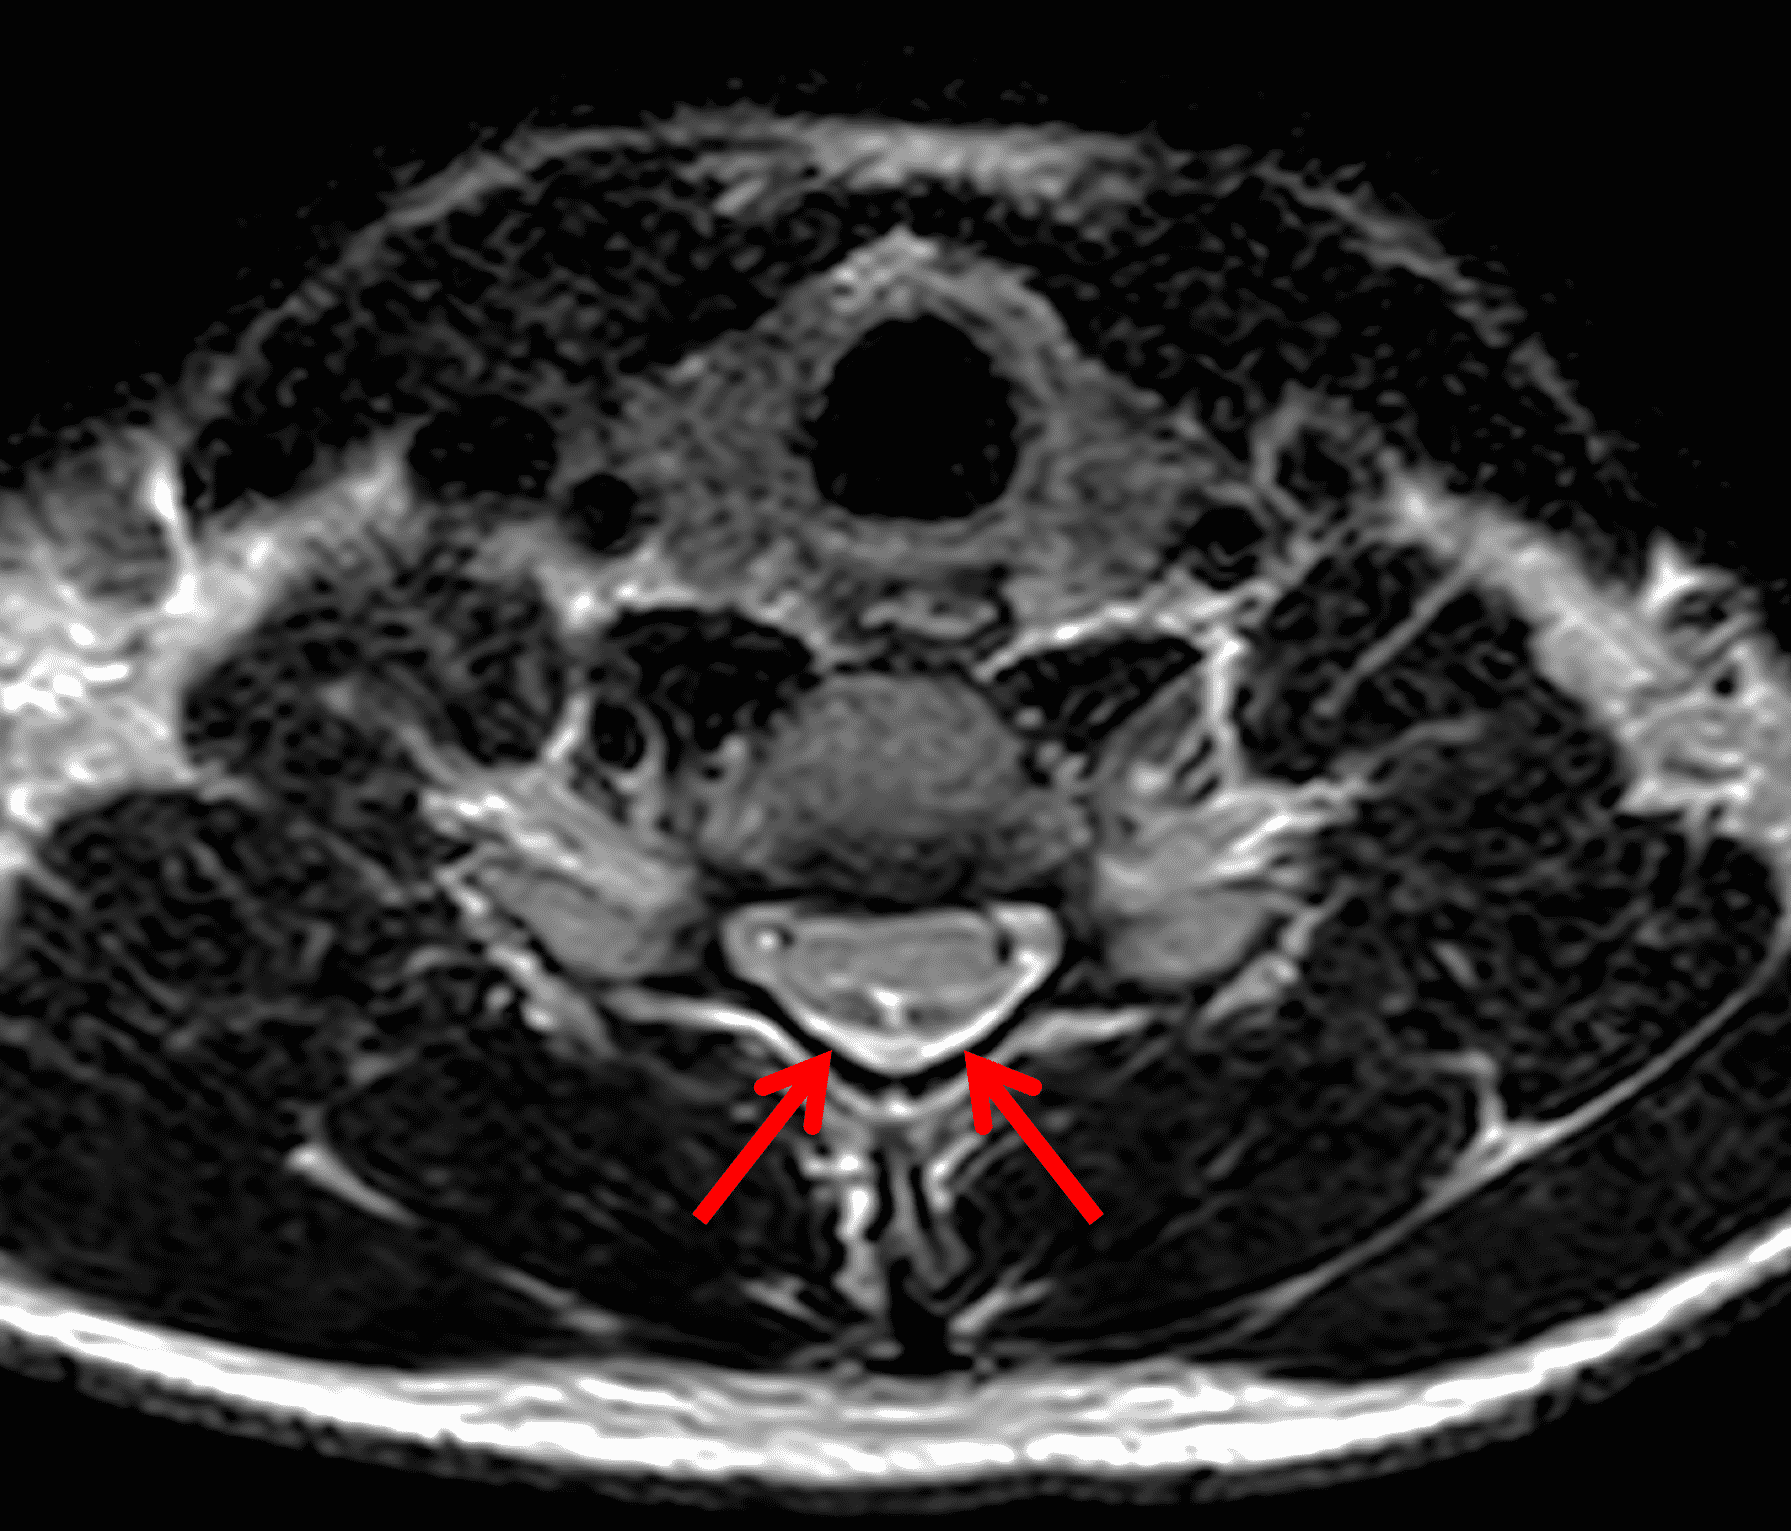

Figure 2: Neutral images of the cervical spine. Sagittal (2A) T2-weighted, (2B) T1-weighted, and (2C) STIR images show mild kyphosis, an enlarged posterior epidural space with loss of attachment of the dura (red arrows), and cord atrophy at the C6 level (yellow arrow). Subtle cord hyperintensity on the water sensitive images at the C7 level (green arrows) likely represents gliosis. (2D) Axial T2-weighted image shows enlargement of the posterior epidural space, right greater than left (red arrows). (2E) Axial T1-weighted image shows an enlarged posterior epidural space (red arrows) and cord atrophy, more severe on the right (yellow arrow).

Chen et al.29 investigated the sensitivity and specificity of these previously suggested neutral position MRI findings and a new proposed finding of loss of attachment (LOA) of the posterior dura from the subjacent lamina. The localized lower cord atrophy and asymmetric cord flattening can be appreciated on axial and sagittal MRI and is most commonly seen at the C4 to C7 levels. This finding is best assessed on axial images since sagittal images may result in erroneous assessment if the cord is not truly at midline. Additionally, comparing axial images to the normal level below is most reliable as the normal cord starts to enlarge at C3, reaches maximum dimension at C5, and tapers below T1. Localized cord atrophy had a sensitivity of 58.7% but specificity of 100% for HD and was not seen in the normal control group.

Asymmetric cord flattening is best assessed on axial T2-weighted images and is defined as cord flattening without narrowed or obliterated adjacent subarachnoid space to avoid confusion with compression due to adjacent spurs or herniated disc. An elliptical spinal cord is considered normal. A pear-shaped cord is seen with asymmetric cord flattening, and a triangular shaped spinal cord is considered symmetric cord flattening. Asymmetric cord flattening was found to have a sensitivity of 69.6% and specificity of 100% for HD.

The LOA sign was proposed as a finding suggesting HD on neutral position MRI of the cervical spine.29 The degree of loss of attachment of the posterior dural sac and subjacent lamina are evaluated on each side of the lamina at C4 to C6 levels on axial T2-weighted images, with separation along more than one-third of the lamina on one or both sides considered positive for LOA. To assess the degree of LOA, the lamina is defined medially by the point of junction of the lamina and laterally by a tangential line along the medial aspect of the pedicle and then divided into three equal parts (Figure 6). The LOA sign was found to have a sensitivity of 93.5% and specificity of 98% for HD. The LOA sign was investigated in the first multisite North American study by Lehman et al.5 and found to have a lower sensitivity of 70% but similar specificity of 100%. The authors confirmed that the LOA sign and other findings are often present on neutral position MRI and in the appropriate clinical scenario, should raise suspicion and prompt further assessment by flexion MRI to confirm the diagnosis.

Figure 6: Axial images demonstrating the loss of attachment (LOA) sign. (6A) T2-weighted and (6B) T1-weighted images in a normal spine (same patient as Figure 3). Yellow lines mark the lateral extent of the laminae, which have been divided into thirds (yellow dots). The posterior dura (red arrows) is firmly attached to the lamina. (6C) T2-weighted and (6D) T1-weighted images of a spine with HD (same patient as Figure 1) show the lamina divided into three equal parts (yellow lines and dots) and displacement of the posterior dural sac, right greater than left, with loss of attachment (red arrows). The separation involves more than one-third of the length of the lamina on both sides.